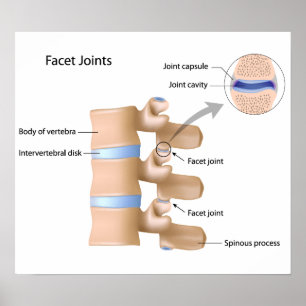

Facetten-gemeinsames Plakat

PreisCHF 61.75